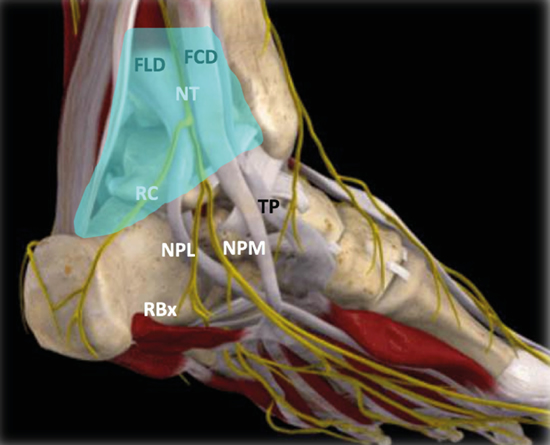

Figura 3. Túnel tibiotalocalcáneo. El nervio tibial (NT) se divide en la rama calcánea (RC), el nervio plantar medial (NPM) y el nervio plantar lateral (NPL) del que se escinde la rama de Baxter (RBx). Las estructuras musculotendinosas tibial posterior (TP), flexor largo del primer dedo (FLD) y flexor largo de los dedos (FCD) acompañan al nervio tibial en su recorrido por la cara medial del tobillo y el pie. Imagen modificada de la App Ankle & Foot Pro III.

Figura 5. Túnel tibiotalocalcáneo. La porción proximal o túnel tibiotalar superior en azul. Estructuras nerviosas: nervio tibial (NT), rama calcánea (RC), nervio plantar lateral (NPL), nervio plantar medial (NPM), rama de Baxter (RBx). Estructuras musculotendinosas: tibial posterior (TP), flexor largo del primer dedo (FLD) y flexor largo de los dedos (FCD). Imagen modificada de la App Ankle & Foot Pro III.